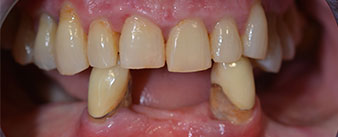

Пациентката е 64-годишна жена с частично обеззъбяване на зъби 38, 33 и 43 и частична долночелюстна протеза (Фиг. 1 и 2).

Необходимото пародонтално лечение и екстракция в челюстта бяха изпълени на по-късен етап, тъй като пациентката е учителка и беше заета с училищни изпити по това време. Тя не можеше нито да се храни, нито да говори нормално, тъй като временната протеза беше много фина и често се чупеше при най-малкия натиск.

След обсъждане на различните възможности за лечение, пациентката реши да се извършат: екстракция в частично обеззъбената долна челюст, имедиатно имплантиране и лечение с Fast & Fixed метод (bredent medical). Временно фиксираната протеза е завита върху четири импланта в същия ден на операцията. Целта беше пациентката да бъде оперирана в петък, за да може да асистира на устните изпити в понеделник.